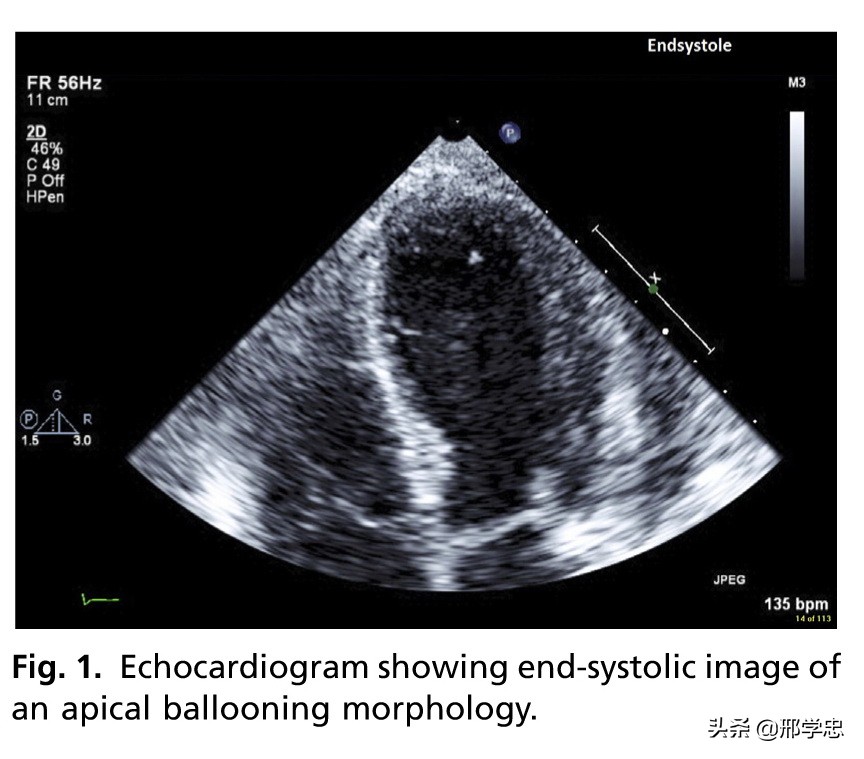

SIC中至少发现3种局部左室壁异常运动,也就是心尖膨大样(图1和图2)、室中膨大样和基底膨大样。心尖膨大样最常见,占70%-80%。室中膨大样和基底膨大样分别占10%-20%和1%-2%。

经胸心动超声是评估可疑SIC患者的一线无创治疗。经胸心动超声联合多普勒超声可以快速评价急性期的左室功能异常(图1),还可以发现潜在的并发症无左室流出道梗阻(图3)和室性血栓(图4)等。这些信息对于患者的成功处理、风险评价和康复的监测是十分关键的。